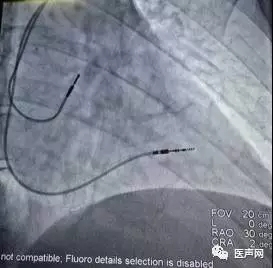

经历了多次后果严重的的晕厥发作,经Reveal证实为心室停搏,患者最终选择了双腔永久起搏器植入(下图),此后尽管腹痛仍偶有发生,但再无晕厥出现。